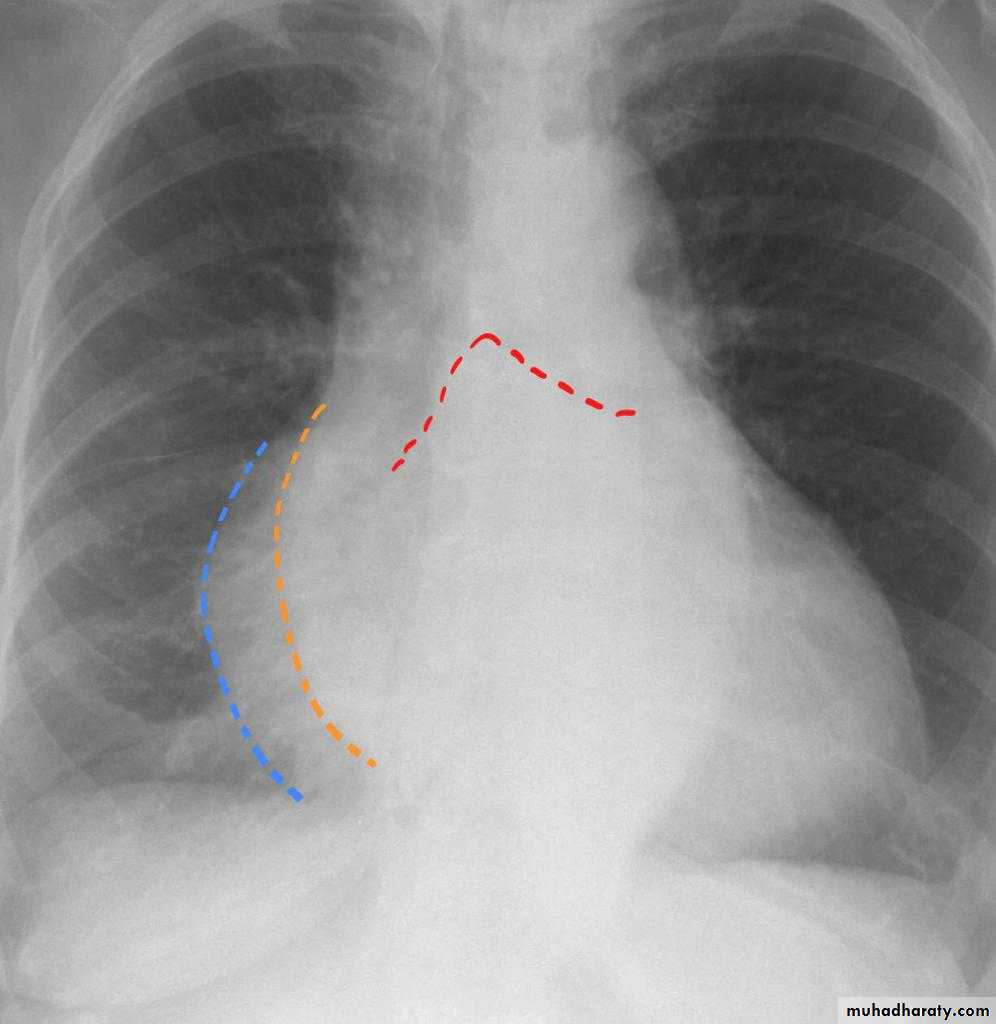

Radiographic featuresPlain film

Typical radiographic features of mitral regurgitation include :

frontal projection

1.left atrial enlargement

convexity or straightening of the left atrial appendage just below the main pulmonary artery (along left heart border)

2.double density sign: the right side of the enlarged left atrium pushes into the adjacent lung and creates an addition contour superimposed over the right heart

3.elevation of the left main bronchus and splaying of the carina

4.upper zone venous enlargement due to pulmonary venous hypertension

5.left ventricular enlargement is also eventually present due to volume overload

6.Features of pulmonary oedema may also be present.

Mitral valve disease